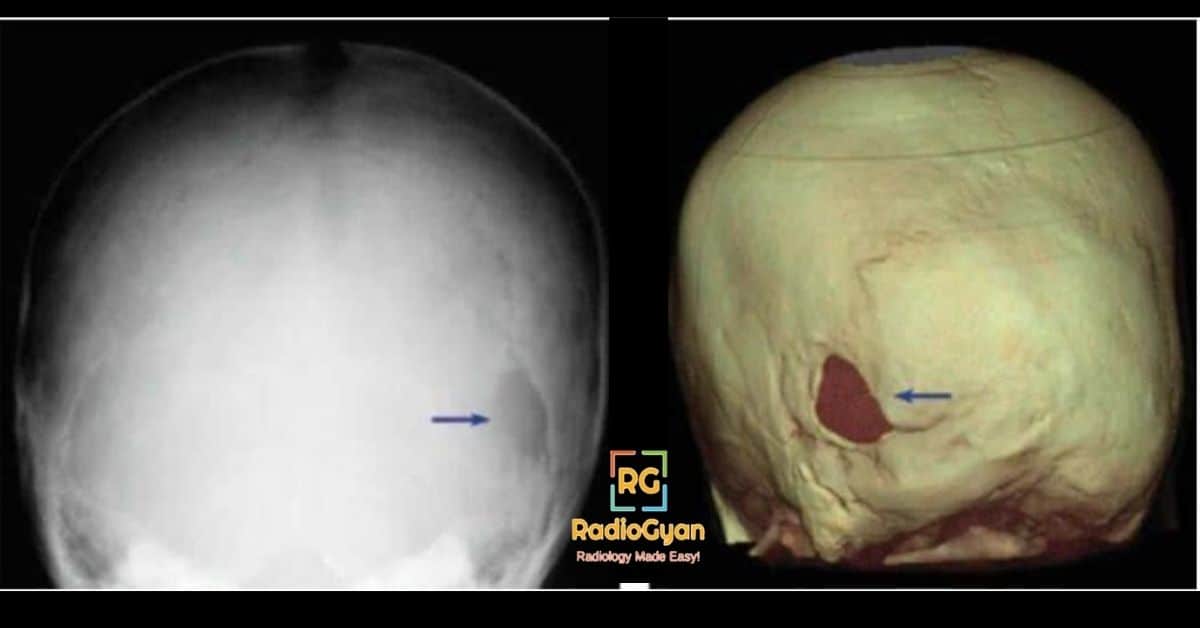

Asterion defect in Neurofirbomatosis 1

• Asterion defect : Lucent defects in the calvarium near the lambdoid sutures (refer image above).